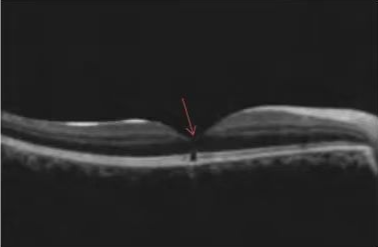

激光笔照射后,黄斑外层细胞—椭圆体带断裂(箭头指向位置)

司法鉴定人通过审阅贾某现有病历资料,进行眼科常规检查、视觉电生理检查,并结合本案具体情况,分析认为:被鉴定人贾某右眼激光笔照射史明确,伤后即出现视力下降,眼底表现为黄斑区出血等新鲜损伤改变,其右眼黄斑损伤与激光笔照射之间存在直接因果关系。

在确认伤情稳定后,司法鉴定人依据《人体损伤致残程度分级》标准,对贾某的伤残等级进行评定。结果显示,贾某右眼黄斑区病变、色素紊乱,并伴有视力明显下降,视觉功能障碍达到“中度视力损害”标准,最终被评定为十级伤残。